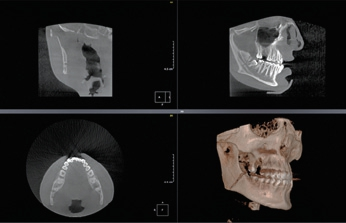

Die Diagnostik in der Zahnmedizin wurde in den vergangenen Jahren durch die Einführung der dentalen Volumentomographie (DVT) erweitert. Dabei hat sich die Indikationsstellung in den letzten Jahren der Weiterentwicklung dieser Technologie angepasst und an Bedeutung zugenommen (Abb. 1). Die dreidimensionale Darstellung der Mund-, Kiefer- und Gesichtsregion visualisiert Informationen, die bei einer konventionellen Projektionsaufnahme aufnahmebedingt nicht dargestellt werden können. Nichtsdestotrotz sind die konventionellen, digitalen Aufnahmeverfahren der Standard in der radiologischen Diagnostik der Zahn-, Mund- und Kieferheilkunde. Die genaue präoperative Diagnostik ist jedoch besonders bei der Detektion und Behandlungsplanung von Tumoren im Kopf-Hals-Bereich von entscheidender Bedeutung. Tumoren in diesem Bereich unterscheiden sich von denen anderer Regionen, da es sich hier um eine hochfunktionale Region mit besonders wichtigen anatomischen Strukturen handelt. Diese Strukturen erlauben in der Regel keine ausgedehnten Resektionen, da diese physiologische Vorgänge extrem beeinflussen würden.

- Die digitale Volumentomographie (DVT) liefert die höchste Auflösung von knöchernen Strukturen, die Darstellung und/oder Differenzierung von Weichgewebe ist jedoch nicht möglich. Vorteile sind die geringen Kosten und die im Vergleich zur CT reduzierten Metallartefakte. Nachteilig hingegen sind der geringe Weichteilkontrast und die Gewebedifferenzierung (Abb. 2 u. 3).

Durch weitere Rechenprozesse können die Daten auf verschiedenste Weise dargestellt werden. Die multiplanaren Rekonstruktionen (MPR) stellen die sinnigste Weiterverarbeitung der Daten dar. Hierbei wird das Volumen durch senkrecht zueinander stehende Ebenen zerlegt, wodurch die Ansichten axial, sagittal und koronal erzeugt werden, ergänzt durch die oberflächengerenderte Ansicht (Abb. 9). Das Angebot entsprechender Bildbearbeitungsprogramme ist vielfältig, zumeist wird das DVT-Gerät mit einer adäquaten Software installiert und eingerichtet – ab diesem Zeitpunkt ist nun der/die Anwender/-in gefordert. In Deutschland ist die Absolvierung eines DVT-Kurses vor Inbetriebnahme eines DVT-Gerätes gesetzlich vorgeschrieben.